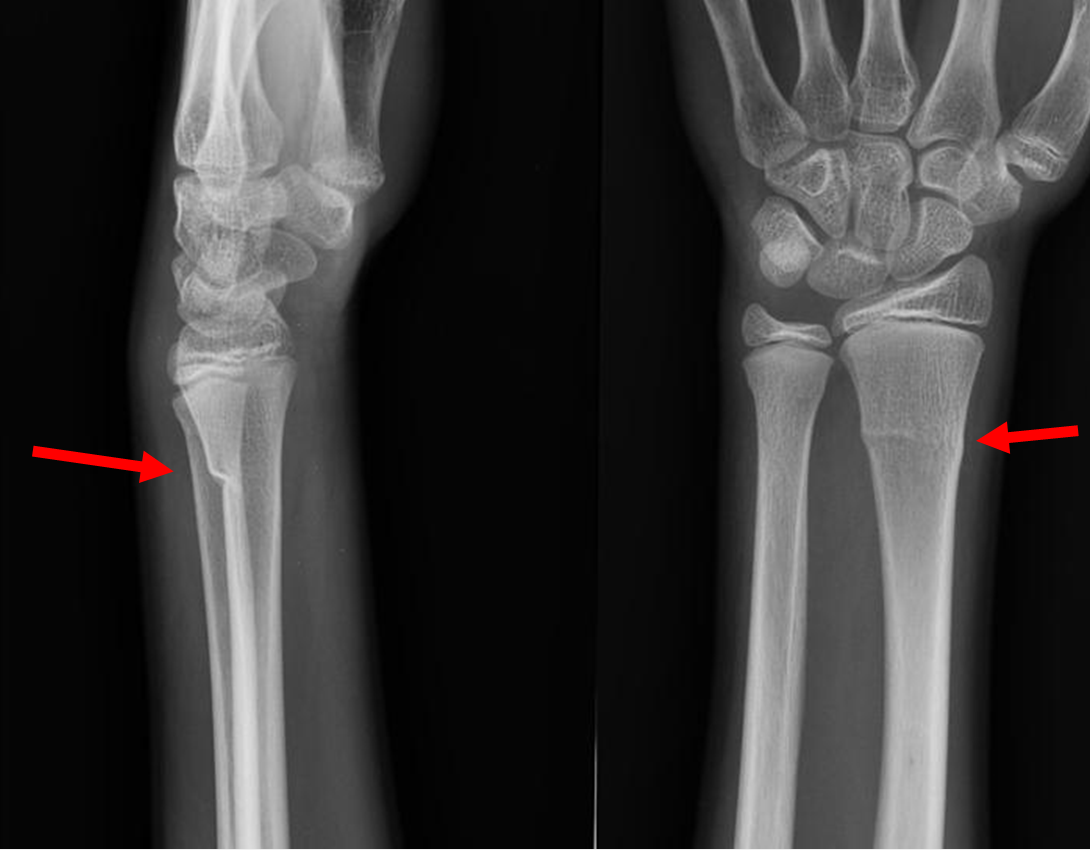

Example xray of distal radius buckle fracture:

Case courtesy of Dr Maulik S Patel, Radiopaedia.org. From the case rID: 10733